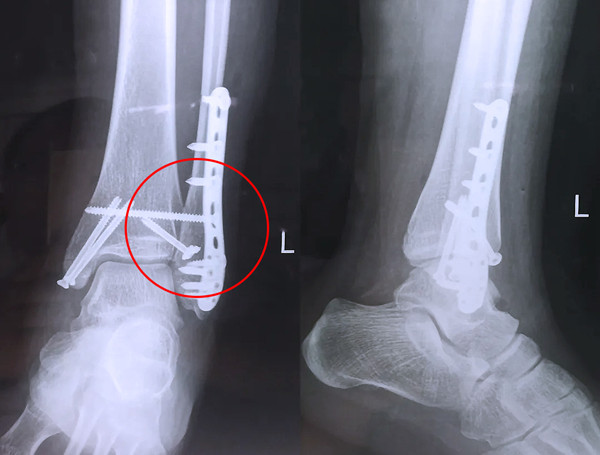

踝关节骨折在X影像上的表现有很多种。如内踝骨折和外踝骨折,我们可以在影像上看到骨折处的骨折线是不连续的?;褂泻篚椎墓钦郏邗?、外踝、后踝联合在一起发生的骨折,我们称之为“三踝骨折”,这些都是在X影像上能够显示出来的。

三踝骨折

【医疗科普】Pilon骨折

有一种特殊类型的踝关节骨折,可能在X影像平片上就不能显示出来,它就是胫骨的关节面往里塌陷,我们又称之为叫“Pilon骨折”。当它往里塌陷后,我们在X影像平片上可能看不出来它是否塌陷,但是我们在CT上可以360°看到踝关节的影像,这样就可以看出患者是否存在踝关节塌陷的骨折。同样道理,我们在做Pilon骨折手术的时候,普通二维的X影像并不能判断我们手术复位情况的好坏,这个时候如果医生手上有能够照三维影像的工具,那么对于医生的准确手术是非常有好处的。